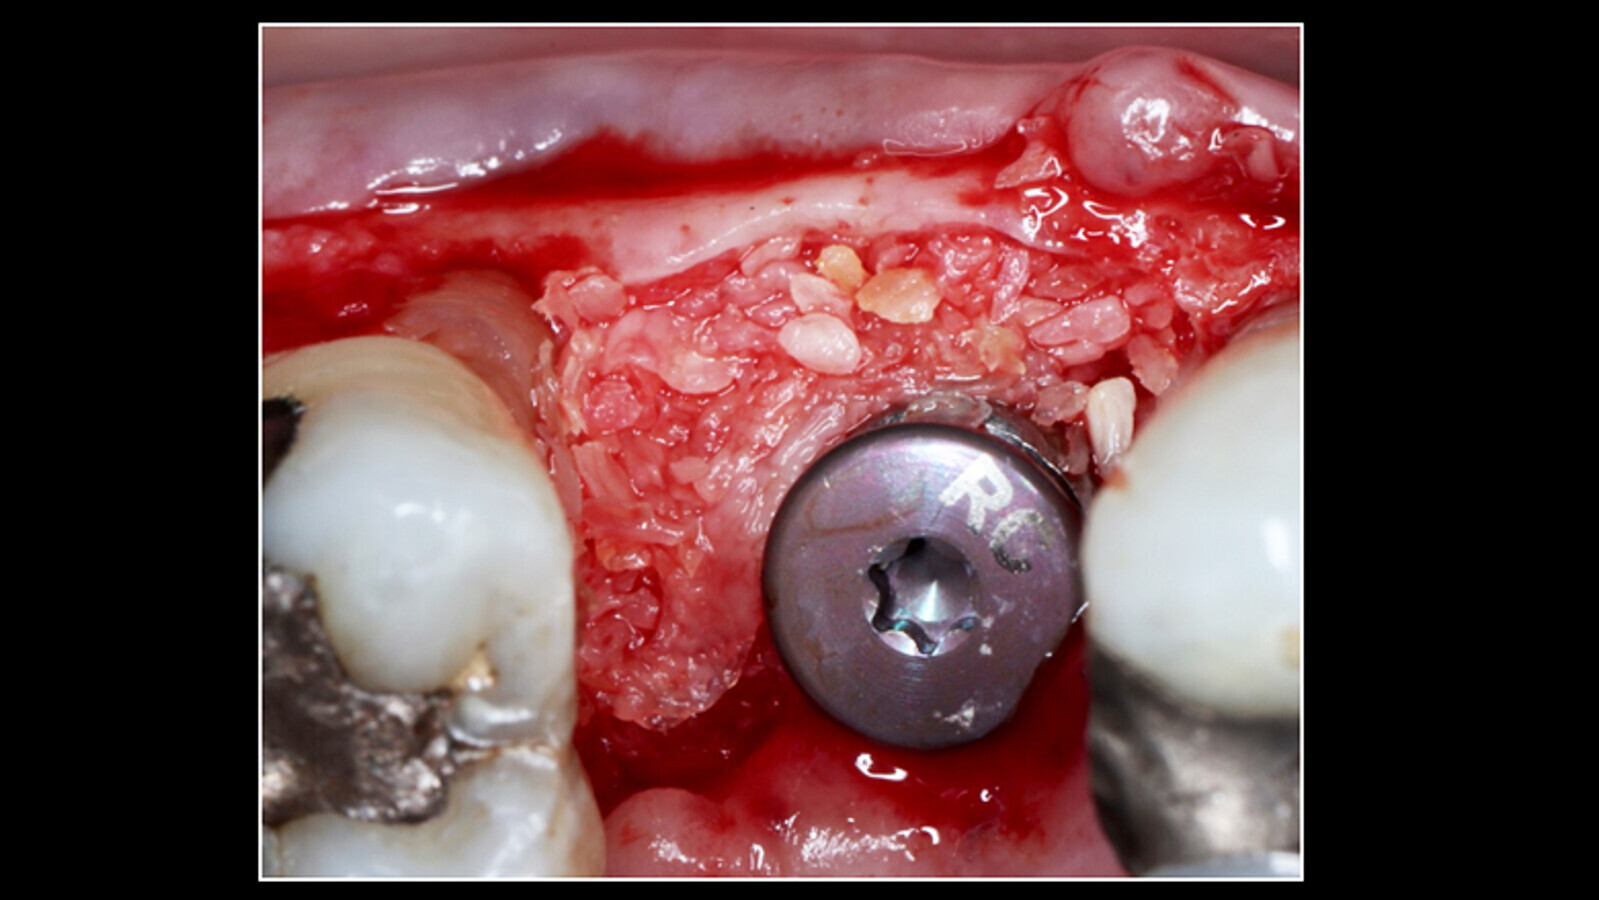

En el defecto óseo periimplantar se injerta un preparado mezcla del aloinjerto Mineroos (Biohorizons, Estados Unidos), plasma rico en plaquetas y fibrina rica en plaquetas y leucocitos L-PRF (Figura 4), con lo que se obtiene tejido conectivo de la zona palatina intervenida, injertándose en la zona vestibular, posterior colocación de membrana de L-PRF, por distal del defecto suturas con AssuCryl 5.0 (ácido poliglicólico, Assut Sutures, Suiza) (Figura 5). Se formula azitromicina 500 mg MK (Tecnoquímicas, Colombia) cada 24 horas por 3 días, acetaminofén más codeína MK, k-cit gel (Laboratorio Farpag, Colombia), aplicado en la herida 3 veces al día. Posteriormente se realizan citas de control cada 5 días para lavado y colocación de láser (6 citas en total).

Figura 4. Injerto en el defecto óseo periimplantar e una mezcla del aloinjerto Mineroos, plasma rico en plaquetas y fibrina rica en plaquetas y leucocitos L-PRF.